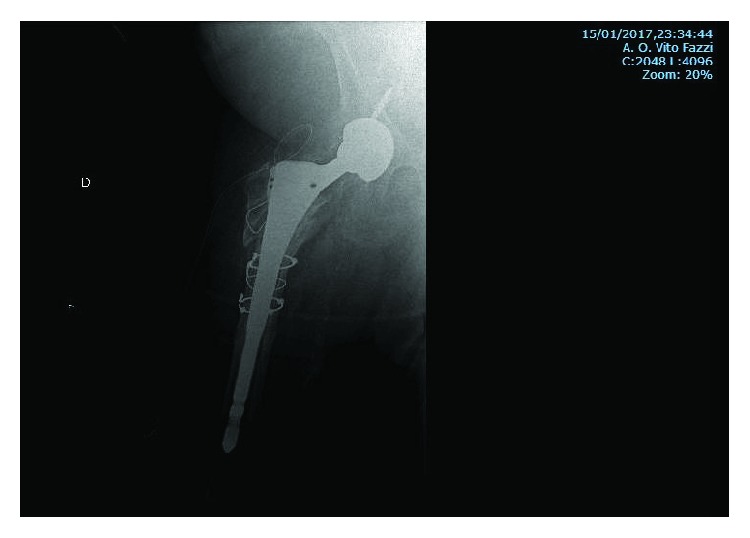

Figure 8.

Postsurgery X-ray, after nail removal and replacement with revision THA with two screws to fix the cup and three metal cable cerclages to prevent the breakage during the implant of the stem.